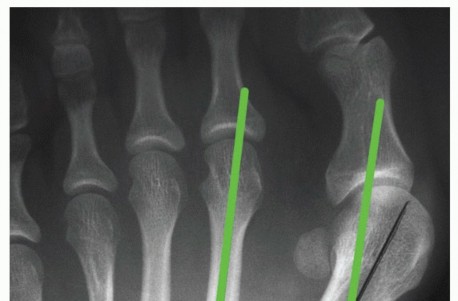

SURGICAL MANAGEMENT Roger A. Mann Jeffrey A. Mann The distal soft tissue procedure and proximal metatarsal os…

SURGICAL MANAGEMENT The primary indication for a proximal closing wedge osteotomy is a symptomatic hallux val…